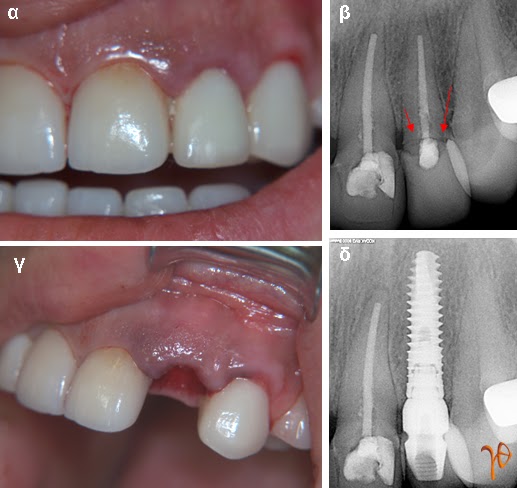

Περίπτωση 3: Άμεση τοποθέτηση και φόρτιση οδοντικού εμφυτεύματος μετά από αφαίρεση του #22 που παρουσίαζε κάταγμα.

Εικόνα 3.1: (α) κλινική εικόνα, (β) το κάταγμα του #22 στην οπισθοφατνιακή ακτινογραφία (βέλη), (γ) μετά την εξαγωγή του #22, (δ) το οδοντικό εμφύτευμα στην οπισθοφατνιακή ακτινογραφία, αμέσως μετεγχειρητικά.

Εικόνα 3.2: (α) και (β) λήψη αποτυπώματος και τοποθέτηση βίδας επούλωσης μέχρι την έλευση της προσωρινής αποκατάστασης, (γ) τοποθέτηση προσωρινής στεφάνης την ίδια μέρα, (δ) μετά από 3 μήνες, η τοποθέτηση της μόνιμης στεφάνης.